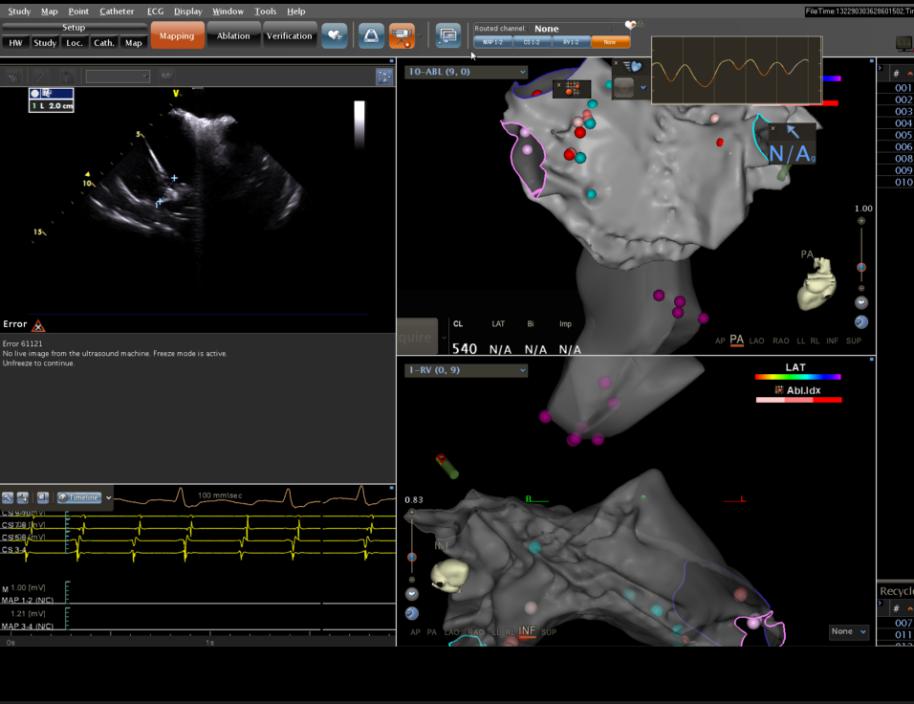

ICE(心腔内超声指导下左心房建模)

术中ICE指导左心耳封堵器植入